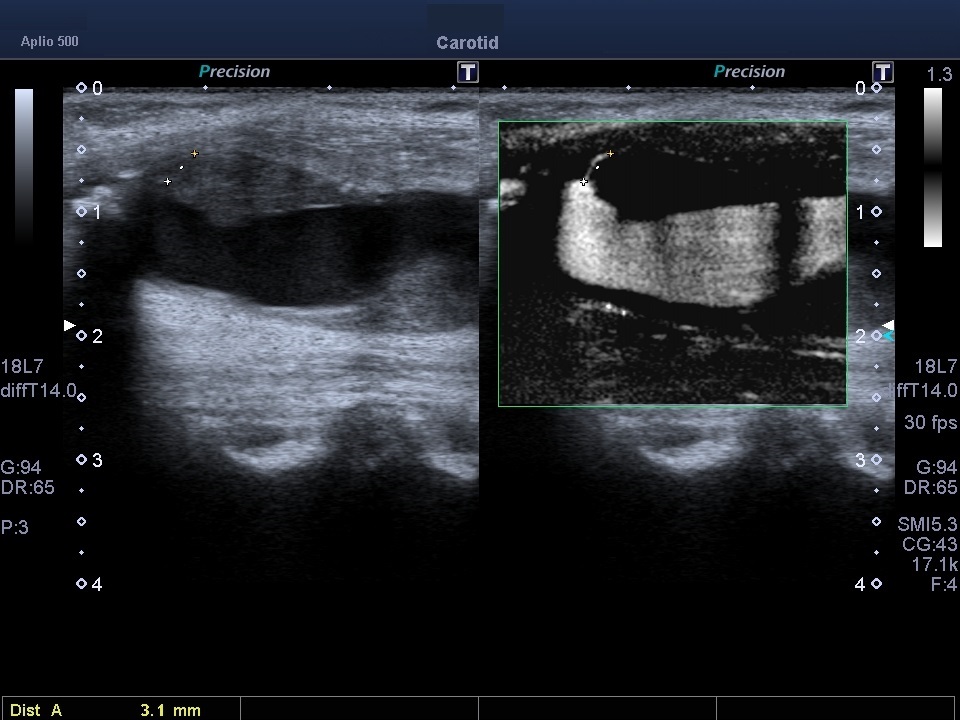

Неінвазивна неоваскуляриція каротидних бляшок з SMI

Значна частка ішемічних інсультів спричинена емболонебезпечними (нестабільними) бляшками сонної артерії з неоваскуляризацією всередині бляшок як ключовою ознакою її нестабільності. Неоваскуляризація не виявляється за допомогою звичайного доплерівського картування. Для проведення такої діагностики може використовуватися ультразвук з контрастом (CEUS, але його використання обмежене в клінічній практиці, оскільки вимагає внутрішньовенної ін’єкції контрасту. Особливу роль відіграє унікальна, неінвазивна, доплерівська мікросудинна візуалізація (SMI) без контрасту, що використовує алгоритм для усунення шумів та рухів стінок, зберігаючи при цьому низькошвидкісні сигнали кровотоку, що дозволяє оцінити ступінь неоваскуляризації бляшок. SMI є перспективною неінвазивною альтернативою CEUS для оцінки стабільності каротидних бляшок.